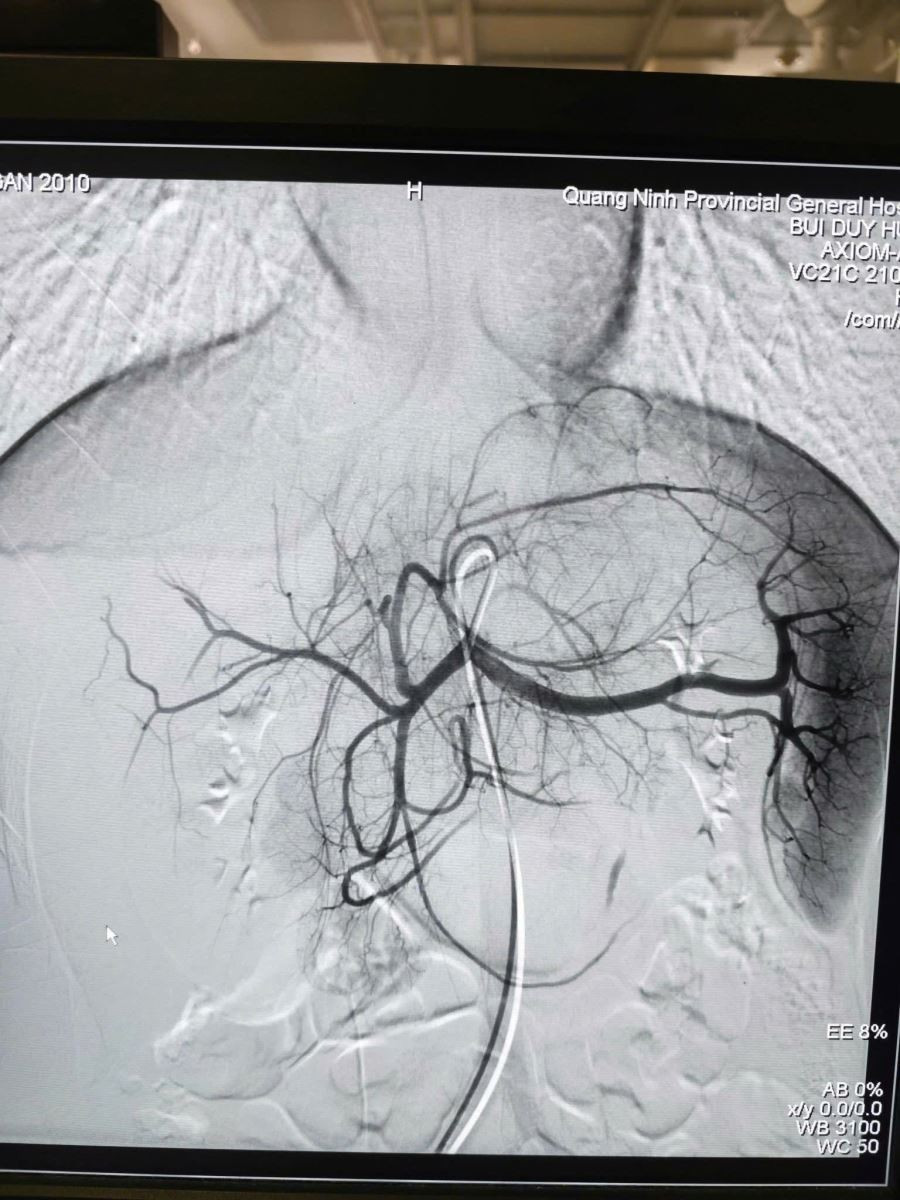

Hình ảnh sau nút mạch điều trị chấn thương gan, ổ chảy máu đã được nút tắc - Ảnh BVCC

Sau 60 phút, ca can thiệp thành công tốt đẹp, hình ảnh chụp kiểm tra cho thấy điểm chảy máu đã được cầm hoàn toàn. Huyết động bệnh nhân ổn định và được chuyển hậu phẫu theo dõi với tiên lượng phục hồi.